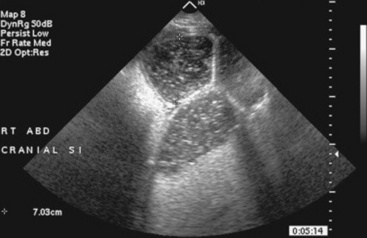

In the last 5 years ultrasound has come to the forefront of evaluation of the equine alimentary tract, primarily centering on the abdomen. Ultrasound has been used in foals to determine the growth rate and normal appearance of thoracic and abdominal organs18 and in adult horses to evaluate the gastrointestinal tract for causes of pain including torsion, small intestinal obstruction, colon impaction, large colon displacement, intussusception, strangulating lesions, and enteritis and colitis.10,19-23 This modality is even more useful because it provides real-time information to help assess contractility of the intestine. Although this has been explored using both standard two-dimension imaging, also called B-mode or brightness-mode imaging, and spectral Doppler imaging,24 the presence of gas within the bowel and the fact that the bowel is usually perpendicular to the image plane makes quantitative evaluation of intestinal contractility difficult at best. When compared with radiography to identify intestinal sand accumulations, ultrasound was found to be 87.5% sensitive and specific using radiography as the gold standard.10 The main limitations are the artifacts secondary to gas within the colon and the fact that gas and mineral are both echogenic on ultrasound, whereas they have opposite opacities on radiographs.

Ultrasound evaluation of horses with abdominal pain (colic) provides a rapid method to identify abnormalities within the gastrointestinal tract. Distention of the small intestine to a diameter greater than 5 cm has been strongly associated with strangulating or obstructing lesions19 (Fig. 32-11). In foals with intussusception, the small intestine appears enlarged and there is generally distended small intestine orad to the lesion; however, at the site of the intussusception there is a normal-appearing small intestinal wall (intussuscipiens) surrounded by a larger structure that appears to surround the inner small intestinal wall (called the intussusceptum)19 (Fig. 32-12). Large colon torsion occurs when the large colon rotates 360 degrees or more around the root of the mesentery to cause occlusion of venous drainage while maintaining arterial flow. This causes the wall to become thick and edematous. If ultrasound is performed in the cranioventral abdomen, just caudal to the xiphoid process, then a colon wall size greater than 9 mm is 100% specific for a large colon torsion21 (Fig. 32-13). A large colon displacement would have minimal to no vascular compromise, so it would be an ultrasound diagnosis based on exclusion. Chronic displacements did have a mild amount of edema in the colon wall, causing the size to be approximately 7 mm thick but never greater than 9 mm in the one study described.21 The colon and small intestinal wall will also become thick with inflammation. Small intestinal wall thickness greater than 4 mm is indicative of inflammation.19 The right dorsal colon can be imaged in the right tenth to twelfth intercostal space around the region of the costochondral junction, and a focal wall thickness of 9 to 12 mm has been identified with right dorsal colitis.23